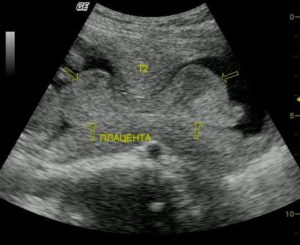

С помощью УЗИ оценивается точное место крепления органа к матке, для исключения его предлежания.

Локализацию «детского места» определяют в ходе каждого скринингового ультразвукового исследования, начиная с 10 недель, но лишь на третьей плановой процедуре УЗИ можно будет окончательно увидеть особенности расположения, и в случае патологического состояния, определить низкое прикрепление плаценты — ее предлежание:

- если отмечается полное перекрытие внутреннего зева матки, то говорят о центральном предлежании «детского места»;

- если внутренний зев перекрыт лишь краем органа — о краевом предлежании;

- если близко к внутреннему маточному зеву — о низком предлежании.

Нередки случаи, когда на втором УЗИ диагностируют предлежание плаценты, однако к концу срока беременности, если не происходит ее отслойка, локализация «детского места» вновь становится нормальной — выше внутреннего маточного зева. Именно поэтому окончательные выводы об уровне локализации орган следует делать только к концу 3 триместра.